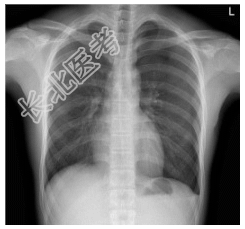

- [材料题] 患者,男性,19岁,突发左胸痛2小时入院。查体.左侧呼吸音减低,深呼吸疼痛加剧,未闻及干湿性啰音。心脏体查无异常。做胸部X光平片检查。

- 简答题1、诊断及依据是什么?

- 简答题2、鉴别诊断有哪些?